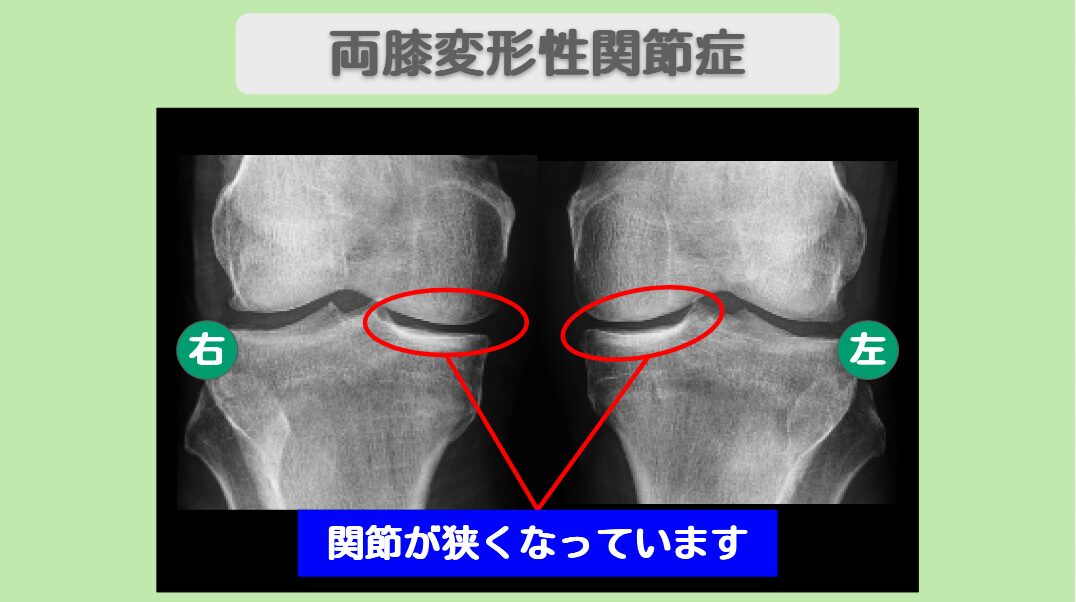

患者様は長年スキーを愛好されており、2006年に左膝半月板手術、2009年に右膝半月板を全摘出された既往がありました。2021年3月にスキー中の転倒で左膝を受傷され、MRI検査では内・外側半月板損傷と、レントゲンで変形性膝関節症(中期)と診断されました。両膝の曲げ伸ばしが辛く、膝の裏側を曲げると痛むという状態でした。

MRI・レントゲン所見